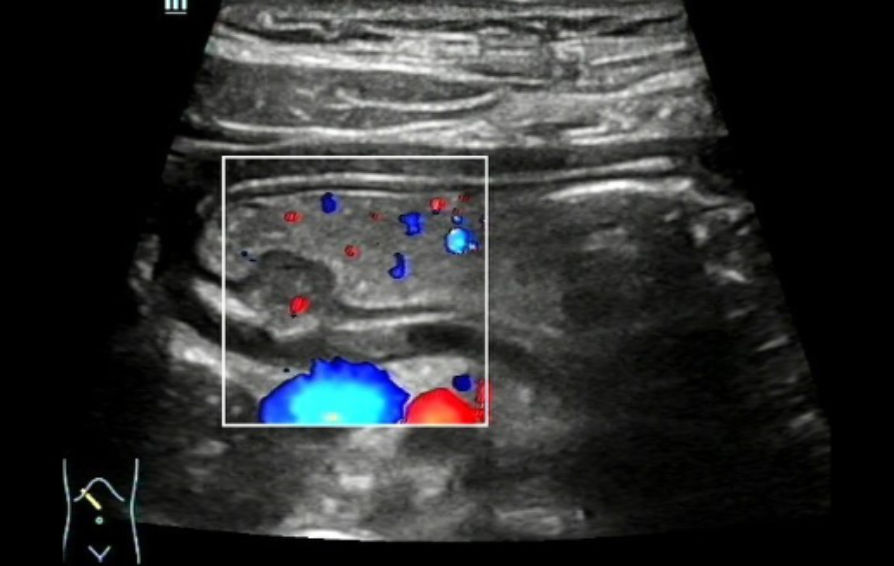

Color Doppler Flow Imaging (CDFI) revealed that a signal indicative of a thin stream of blood flow could be identified near the base of the mass. (Figure 4). Ultrasound indicated a submucosal occupying lesion in the stomach, and ectopic pancreas was suspected.